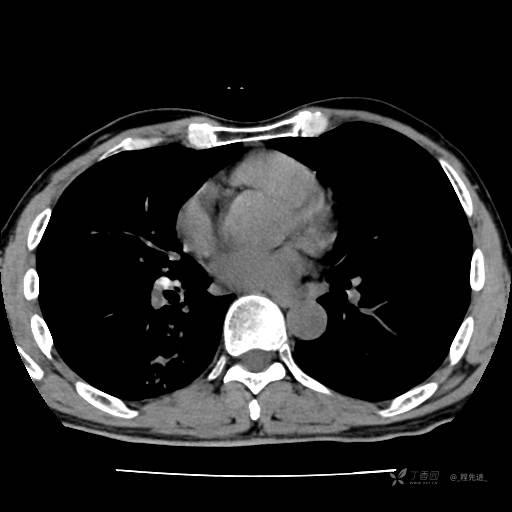

2月特别精彩病例|咳嗽、咳痰20余天,典型病例分享【结果已公布】

患者年龄:51岁

主诉:咳嗽、咳痰20余天

简要病史:20余天前开始出现咳嗽、咳痰症状,阵发性刺激性咳,白色粘痰,不易咳出,无发热,无咯血,无恶心、呕吐等不适,未诊治,咳嗽、咳痰症状持续存在。

体格检查:T:36.3 ℃ P:79 次/分 R:20 次/分 BP:128/64 mmHg,神志清楚,呼吸平稳,双肺呼吸音粗,右下肺闻及细湿性啰音。心率79次/分,节律整齐,各瓣膜听诊区未闻及病理性杂音。腹部未见异常,双下肢无水肿。

辅助检查:我院门诊胸部CT示:如下。心电图:窦性心律;正常心电图。